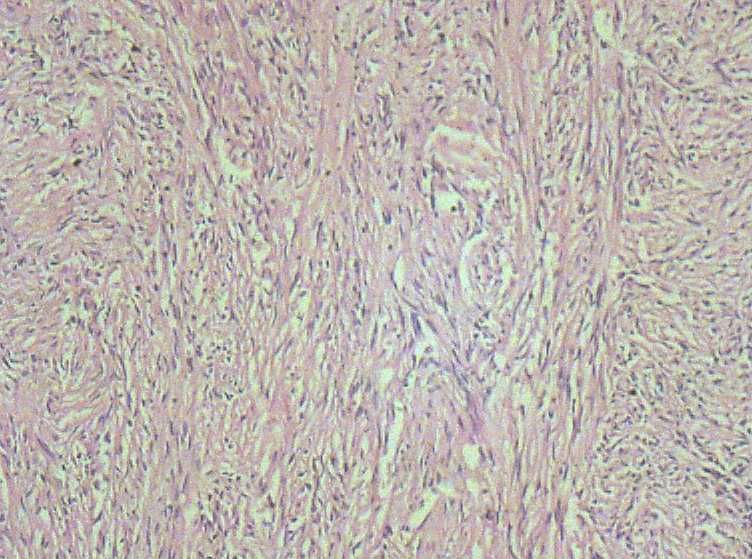

女40岁,发现乳房皮肤表面一年多。

肉眼:不整形组织1.5*1*0.5一侧见皮肤或一侧可见脂肪,切开内一小结节触之稍韧。

良性病变。

炎症后的瘢痕结节或者纤维组织瘤样增生?

皮肤纤维瘤

倾向于皮肤纤维瘤。